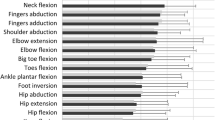

In 102 patients (21 immune-mediated necrotizing myopathy/IMNM, 21 inclusion body myositis/IBM, 10 GNE myopathy/GNEM, 19 Duchenne muscular dystrophy/DMD, 12 dysferlinopathy/DYSF, 7 limb-girdle muscular dystrophy/LGMD2I, 7 Pompe disease, 5 spinal muscular atrophy/SMA), two MRI scans were obtained at a 1-year interval in thighs and lower legs. Regions of interest (ROIs) were drawn in individual muscles, muscle groups, and the global muscle segment. Standardized response means (SRMs) were determined to assess sensitivity to change in fat fraction (ΔFat%) in individual muscles, muscle groups, weighted combinations of muscles and muscle groups, and in the global muscle segment.

Global muscle segmentation gave high SRMs for ΔFat% in thigh and lower leg for IMNM, DYSF, LGMD2I, DMD, SMA, and Pompe disease, and only in lower leg for GNEM and thigh for IBM.

Global muscle segment Fat% showed to be sensitive to change in most investigated neuromuscular disorders. As compared to individual muscle drawing, it is a faster and an easier approach to assess disease progression. The use of individual muscle ROIs, however, is still of interest for exploring selective muscle involvement.